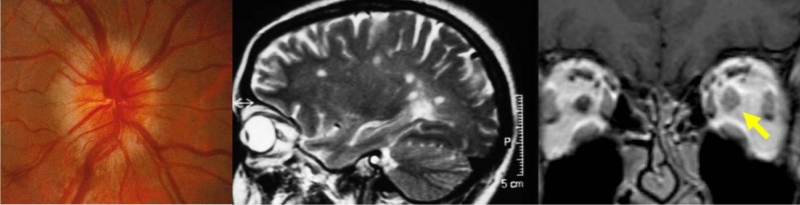

- Neuritis óptica anterior / papilitis

Se presenta con pérdida visual, defecto pupilar aferente y dolor periorbitario que aumenta con los movimientos oculares asociado a edema de papila. El estudio se dirige a las enfermedades desmielinizantes, principal etiología de las neuritis. La prueba de imagen de elección es la RM craneal y orbitaria con finalidad diagnóstica, pronóstica (mayor riesgo de desarrollar esclerosis múltiple si aparecen lesiones características), y evolutiva (el realce de las lesiones con contraste sugiere enfermedad en fase aguda). Las secuencias FLAIR son las más adecuadas para mostrar las lesiones desmielinizantes (Figura 4). La RM orbitaria puede obviarse en casos muy típicos de neuritis con lesiones desmielinizantes en la RM craneal.

Figura 4. Izquierda: edema de papila en neuritis óptica típica. Centro: lesiones desmielinizantes en RM craneal (T2). Derecha: engrosamiento del nervio óptico izquierdo en RM orbitaria (T1)

En los casos atípicos sigue estando indicada una RM craneal y orbitaria, asociando otras pruebas complementarias según la sospecha diagnóstica (serologías, marcadores de autoinmunidad, punción lumbar, etc.). Las secuencias T1 con supresión grasa son las más adecuadas para apreciar el realce en la porción orbitaria del nervio óptico. La RM espinal se indica por la sospecha de neuromielitis óptica: episodios recurrentes de neuritis óptica anterior o retrobulbar con menor recuperación visual de lo esperado, asociados o no a mielitis transversa, y cuya RM craneal no es compatible con esclerosis múltiple (EM) (Figura 5).